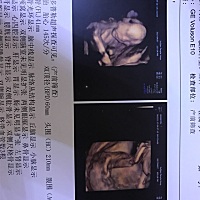

能看出来男孩女孩吗